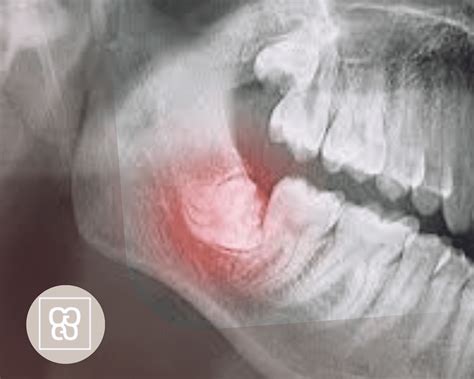

La causa más común para considerar la extracción de las muelas del juicio es que no puedan emerger completamente debido a que no tienen espacio en el maxilar. Impactación: dado que son las últimas piezas dentales en salir, es frecuente que las muelas del juicio no puedan erupcionar completamente debido a la falta de espacio en la boca. Además, en muchos casos, la muela del juicio se encuentra en una posición que dificulta su salida.

Cuando las muelas aparecen en la encía de manera parcial, suelen crear áreas difíciles de ver y limpiar donde se acumula comida, placa bacteriana y suciedad que puede atraer a bacterias, incrementando el riesgo de sufrir caries o infecciones orales. La falta de espacio para el crecimiento adecuado de las muelas del juicio puede generar diversos problemas, como dolor, infecciones, quistes, daño a los dientes adyacentes y maloclusiones.

En otros casos, las muelas del juicio pueden salir con una inclinación horizontal, apiñándose con dientes cercanos, a los que pueden acabar dañando. A veces, la vía de erupción de las muelas del juicio es correcta, pero si los maxilares no tienen suficiente espacio para albergarlas puede que no lleguen a emerger, y queden retenidas en la mandíbula. Infecciones recurrentes: las muelas de juicio se pueden infectar debido a caries o a una pericoronaritis.

Cuando las muelas del juicio no logran erupcionar completamente o lo hacen de forma parcial y en una posición inadecuada, se les denomina “muelas del juicio impactadas” o “incluidas”. A veces, las muelas del juicio pueden causar diversos problemas, como impactación, dolor e infección.